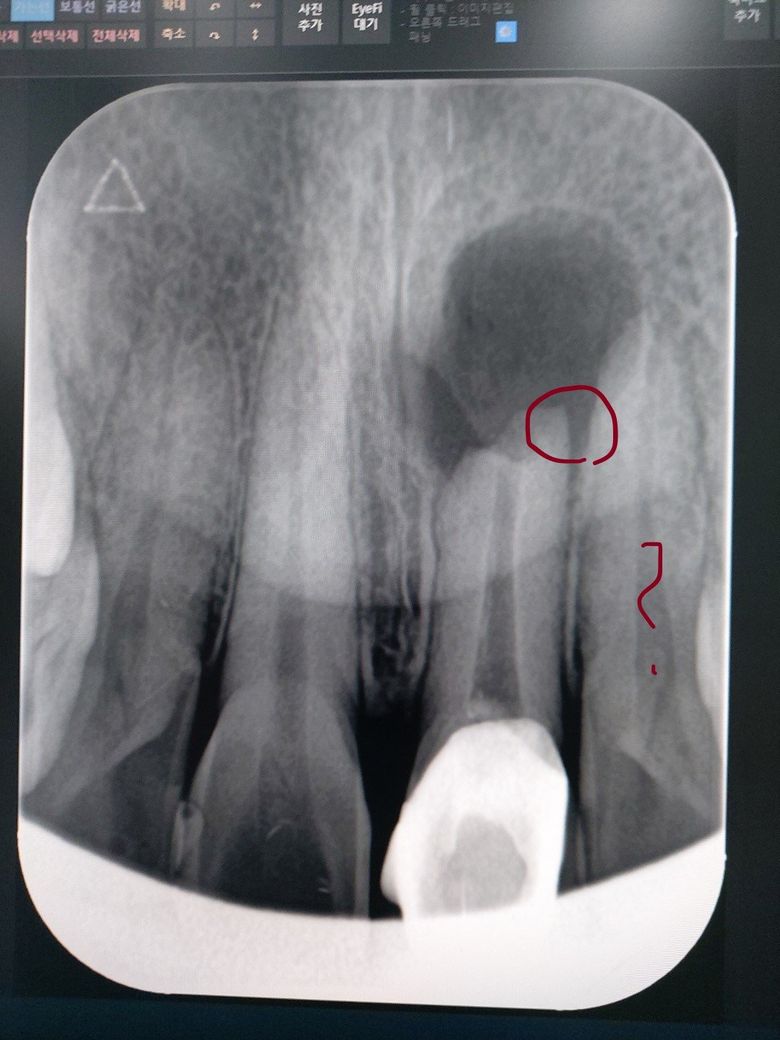

치근단염 재발 후 옆이빨 상태 좀 봐주세요

문제는 옆 이빨 상태 확인 좀 부탁 드립니다

염증이 넘어 간 걸까요?

최근에 동그라미 곳에 찌릿하는 통증도 있습니다

""치근단절제할 때 잇몸에 버로 둥글게 구멍을 내는데 이게 옆 치아까지 보이게 구멍을 뚫었어요. 이유가 염증제거를 같이 진행하는데 옆에 까지 번져서 그런 것 인지 아니면 잘못 제거한 것인지 알 수가 없네요.""

라고 했습니다

파노라마 사진상으로는 크게 문제가 없어 보이기는 하나 파노라마 사진은 3차원 구조를 2차원으로 표현하기 때문에 상당한 왜곡이 있습니다. 사진만으로 보아서는 괜찮아 보이지만 정확한 판단을 위해서는 dental-CT 등을 촬영하여 3차원적인 구조를 파악해볼 필요가 있어 보입니다. CT를 촬영하고 이를 평가받았는데 문제가 없었다면 말씀하신 치아에 영향은 없을 것으로 보입니다.

치근단 사진은 2차원적으로 보이기 때문에 옆의 치아를 침범한것이 실제로 침번함것이 아닌 앞이나 뒤의 뼈의 양이 적기 때문일수 있습니다.

엑스레이 사진상으로는 옆치아도 문제가 생길수도 잇을것같습니다. 아마도 염증이 퍼졋을 가능성이 있습니다. 하지만, CT상으로 확인을 하셧다면 CT가 더 3차원적으로 볼수 있으니, 그게더 정확합니다. 일단은 염증이 이환된 치아를 먼저 치료 받으신느게 중요할꺼 같습니다.

치근단수술을 한 치아의 옆치아는 문제가 없어보입니다. 까맣게 보이는 염증은 크라운 한 치아의 염증때문에 그렇게 보이는것이고, 염증의 원인치는 크라운 한 치아이기 때문에, 원인치를 발치하거나 재치료해서 염증이 제거될 수 있다면, 그 옆치아부분은 방사선사진으로도 괜찮게 보일 것으로 보입니다.

만약 옆의치아에 염증이 있는것이라면 분명 그 치아에 증상이 있을것입니다. 가만히 있어도 아프다거나, 치아색이 변했다거나 흔들리는 등의 증상이 있을 것입니다. 보통은 한 치아의 치근단염증이 심한경우 엑스레이 상으로 옆의 치아까지 번진것처럼 보이는 경우는 흔합니다.

사진으로 보기에는 2개 치아에 걸쳐 치근단 염증이 있어 보입니다.

이런 경우 치근단 절제술로 치근단 염증 긁어 낼 때 치아 2개를 같이 하는 경우도 있습니다.

1개 하느냐 2개 하느냐는 수술 하면서 육안으로 직접 보고 판단해야 하는 경우가 많습니다.